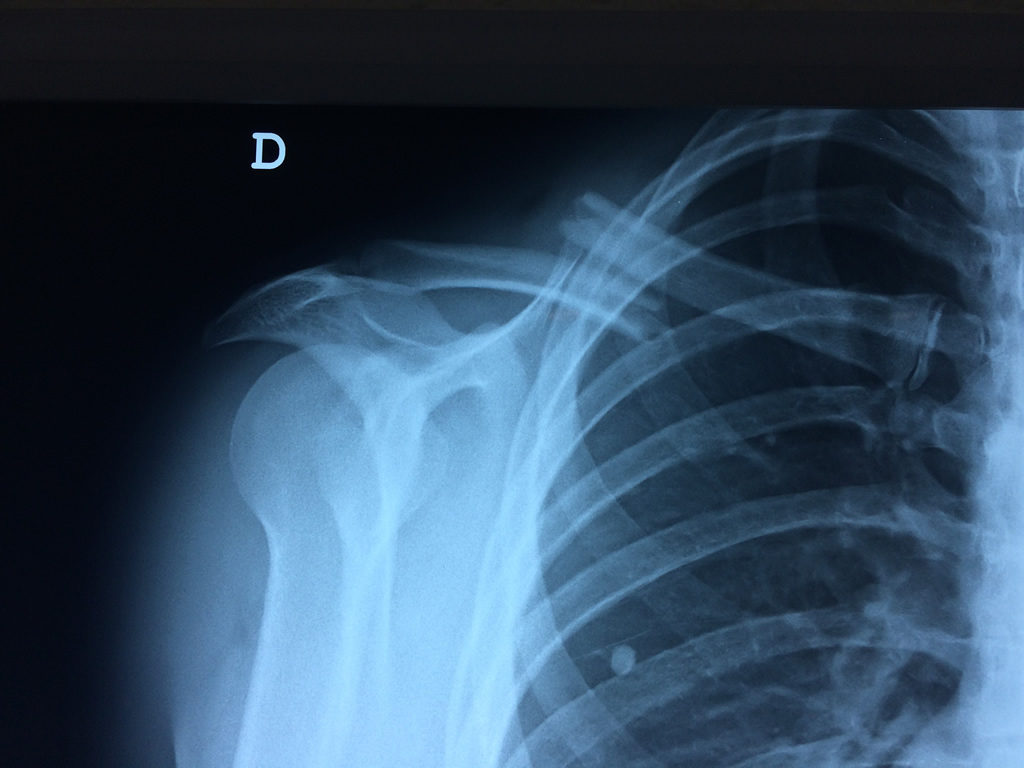

Cirugía de Fémur - Clavícula

La clavícula es un hueso largo, con forma de "S" itálica, situado en la parte anterosuperior del tórax. Junto con la escápula forman la cintura escapular. Se puede palpar por toda su longitud y se extiende del esternón al acromion de la escápula, siguiendo una dirección oblicua lateral y posterior.

Se considera el único medio de unión entre el miembro superior y el tórax. A pesar de su aspecto, similar al de un hueso largo, posee una estructura semejante a la de un hueso plano, ya que carece de epífisis y de diáfisis, lo que la harían entrar dentro de la clasificación de hueso largo. Carece de un canal medular propiamente dicho.